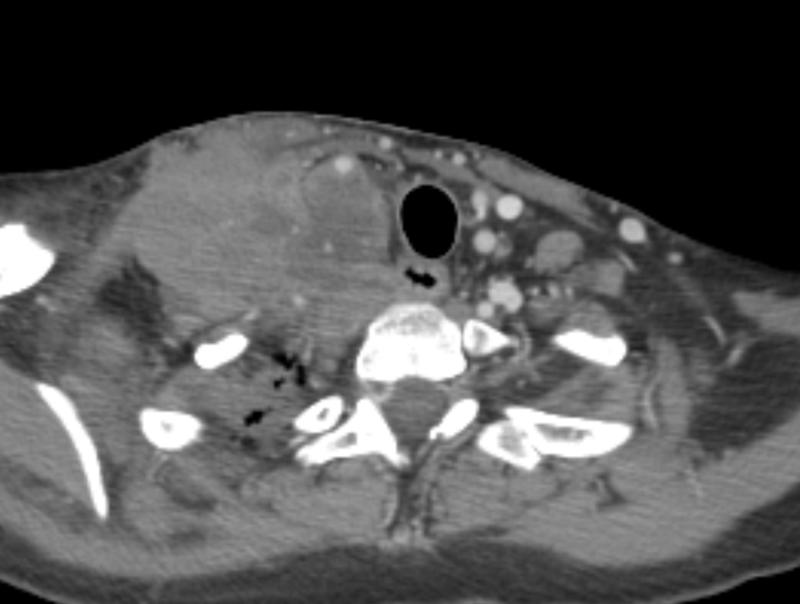

lymphoma (NHL) axial CT